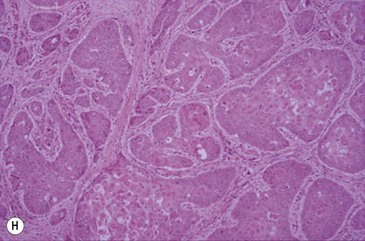

(G) This horse was presented with weight loss and dysphagia. The highly destructive oral and invasive carcinoma was not visible endoscopically from the pharynx and was only seen with difficulty during an oral examination. (H) Photomicrograph of cords of solid squamous cell carcinoma with deep invasion of the tongue. (I) Metastasis of squamous cell carcinoma to regional lymph node showing cords of tumor cells (arrows) beneath cortical lymphoid tissue.

Pathology

Histologically, the tumor has distinctive characteristics with irregular cords of downward-invading neoplastic keratinocytes. (Figs 11.13H,I). A SCC characteristically has large amounts of non-neoplastic fibrous stroma in which inflammatory cells are plentiful. The abundant stroma results in a lesion that is characteristically tough or scirrhous when palpated or excised. The accumulation of variable amounts of keratin produces ‘keratin pearls’ in well differentiated tumors that can be used to define the likely malignancy of the lesion. Poorly differentiated carcinoma shows a more anaplastic cell structure, higher rates of division (high mitotic index), and much less keratin and, therefore, can closely resemble aggressive myxosarcoma. SCC is one of the better defined equine oral neoplasms.